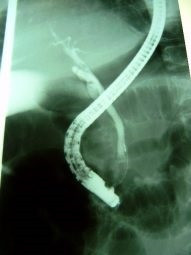

Coledocolitiasis pancreatitis biliar

Envíado por Dr. Carlos Miguel Zavaleta Consuegra